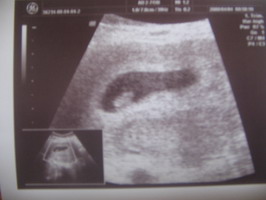

Na csajok!Itt van a kistesó! :D Dobogó szívvel :!: 6 hetes és 5 napos :D Imádom :!: :D :D :D Nem ítéltek fogyókúrára a tanácsadáson,de mivel a Hannával 25 kg-ot híztam,most azt mondták elég lesz a fele is :)